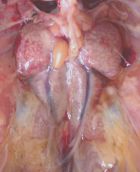

نام بیماری : کلی باسیلوز

سبب شناسی : اشر شیاکلی

نشانیها : کیسه هایی هوایی ضخیم میشود و ترشحات پنیری شکل دیده میشود . اغلب همراه با آن پریکاردیت چسبنده ایجاد میشود . تشخیص با استفاده کشت میکروبی قطعی میشود

درمان :رعایت بهداشت در گله و جلوگیری از استرس در پیشگیری موثر است .کلرامفنیکل ٬فورازولیدون در درمان آن موثر است ولی توصیه می گرددکشت میکروبی و آنتی بیوگرام انجام گردد